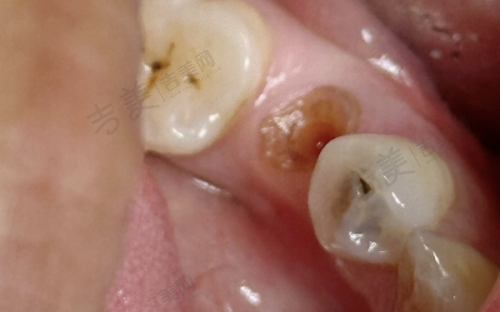

丰富手术项目:上海雅杰口腔诊所诊疗项目丰富,规模适中且科室设置较为齐全。其诊疗科目涵盖口腔科、牙体牙髓病、牙周病、口腔粘膜病、儿童口腔、口腔颌面外科、口腔修复、口腔正畸、口腔种植、预防口腔,还有医学影像科的X线诊断。在手术方面,诊所擅长种植牙手术,无论是前后牙种植,还是内/外提、各类骨增量、穿翼、半/全口即刻种植手术都能熟练开展;牙齿矫正手术也特别出色,包括成人正畸和儿童早期干预;牙齿修复手术同样是其优势,如全口活动义齿修复、美学修复等;此外,在各类阻生智齿拔除、规范化根管治疗、牙周治疗等方面也有丰富的经验和专精的技术。凭借这些优势手术项目,为不同口腔问题的患者提供了有效的治疗方案。

特色科室与项目:上海雅杰口腔诊所的科室设置和特色项目优势明显。科室方面,有口腔科、牙体牙髓病科、牙周病科等多个专精科室。特色项目包括种植牙、牙齿矫正、牙齿修复、儿童牙齿治疗等。种植牙项目采用数字化种植,拥有3D导板种植系统,可精细定位种植位置,减少创伤,修复更快。牙齿矫正中的隐形矫正使用口内扫描仪,5分钟扫描取模,不用咬恶心的石膏,还能即时出3D矫正方案。牙周治疗采用超声波洁牙机 + 激光治疗仪,洁牙更干净,激光消炎减少出血,不适感轻。儿童补牙配备疼痛较小局麻仪 + 卡通牙钻,缓慢给药减少疼痛,卡通造型缓解孩子紧张。这些特色项目凭借精良的设备和专精的技术,为患者提供了优质的口腔治疗体验。